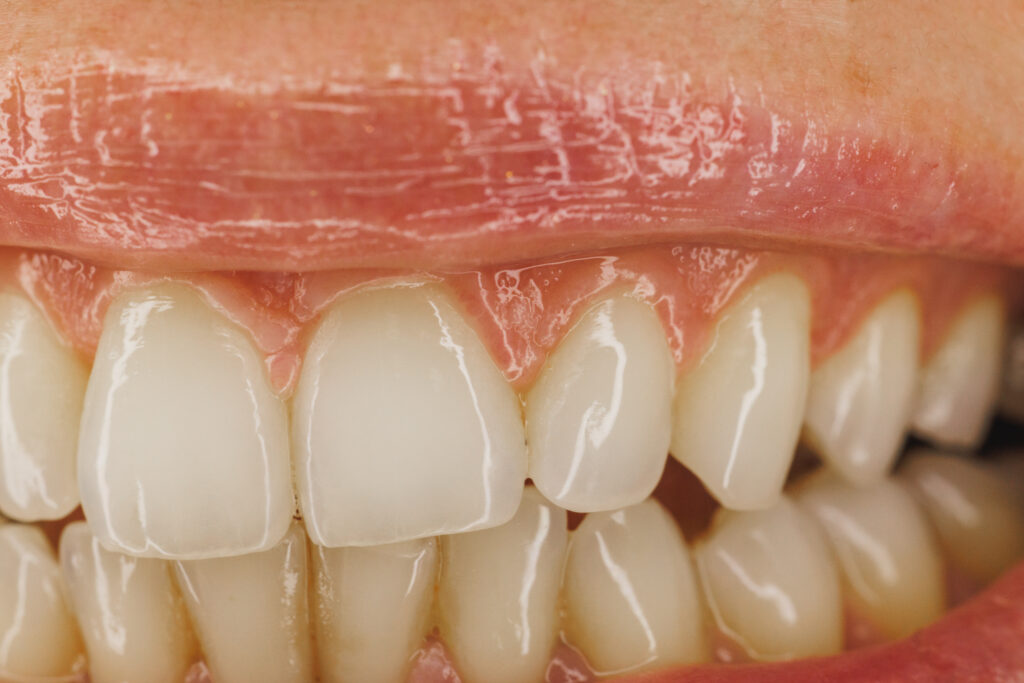

Why Do I Have To Go For 6-Monthly Dental Cleanings (Especially If I Have A Dental Implant)?

6-monthly dental cleanings help protect your teeth, gums and existing dental restorations.